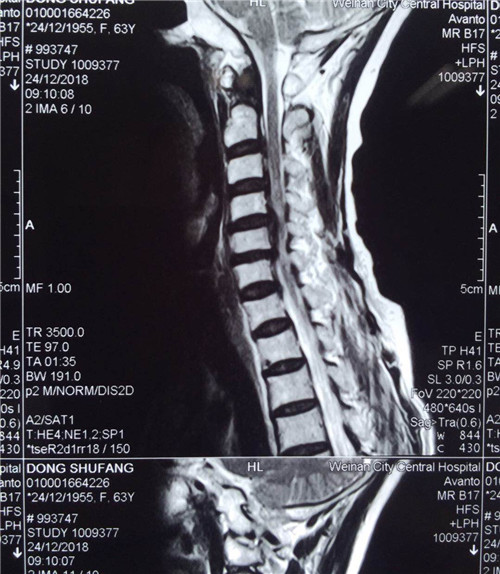

术前

患者入院后,骨一科医护人员为其做进一步检查,诊断为多发颈椎间盘突出并继发颈椎管狭窄症。经讨论研究后,程福宏副主任医师决定为其行颈后路颈4、5、6的单开门椎板扩大成形术,该手术在王小峰主治医师的配合下完成。术中,医生为患者进行彻底的减压脊髓,固定椎板。术后患者恢复较好,症状改善明显,已能够独自行走,恢复正常活动。